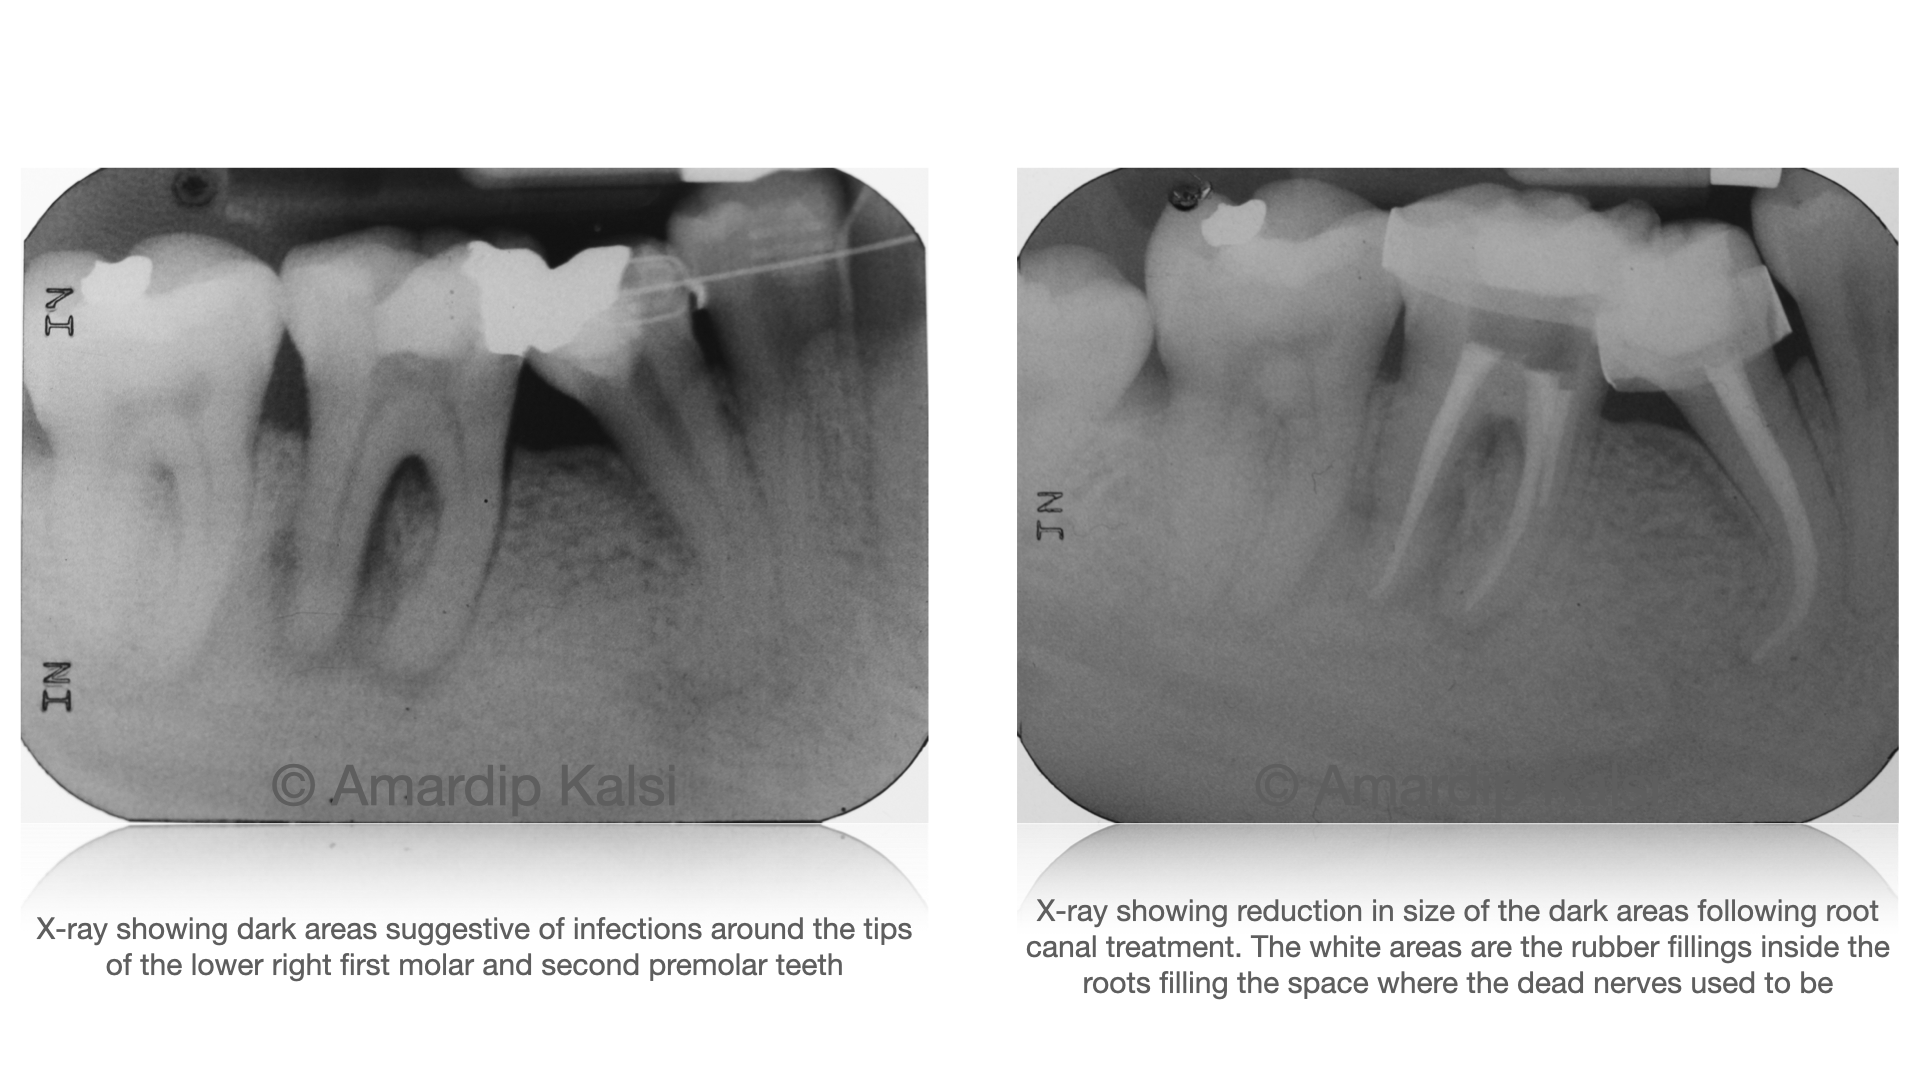

Problems like decay, tooth wear, trauma and gum disease can result in the nerve inside a tooth to die and in turn an infection at the tip of the root of the tooth to occur. Occasionally, short-term symptoms can be managed with antibiotics, however definitive resolution of the infection can only be achieved with tooth removal or root canal treatment.

Despite common misconceptions this treatment is painless for an overwhelming majority of patients. This involves drilling into the tooth and cleaning out the dead nerve with small instruments and irrigating solutions. Following this rubber fillings are placed in the space that the nerve used to occupy, followed by a normal dental filling above this. For posterior teeth a crown is usually indicated afterwards as the tooth will be more brittle and prone to breakage.